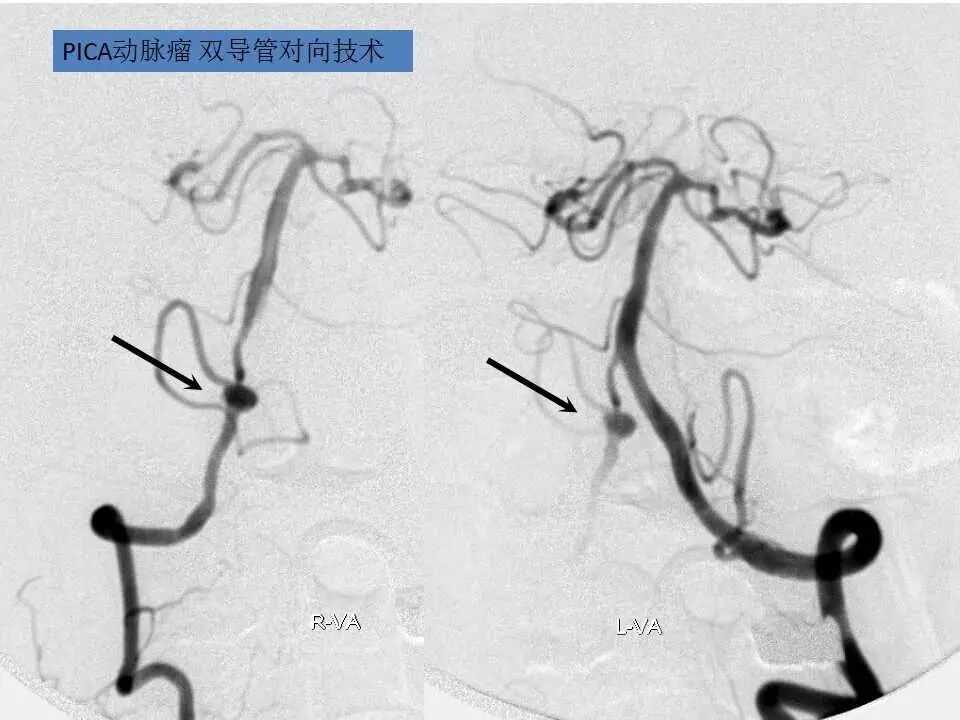

今天为大家分享的是“强生医疗CNV-神经介入专栏”第十五期,由首都医科大学宣武医院何川教授带来的“颅内动脉瘤介入治疗”精彩讲课视频及PPT,欢迎观看、阅读。文章仅代表作者个人观点,如有不同见解,欢迎同道斧正!

何川 ,首都医科大学宣武医院副主任医师,中国医师协会神经介入专业委员会常务委员,长期从事脑血管病和脊髓血管病的手术及介入治疗和相关研究工作。首都医科大学神经外科博士,师从于中国神经介入开创人凌锋教授;日本东北大学医院脑血管病治疗科博士后,师从于日本国脑血管病血管内治疗的开创者高桥教授。